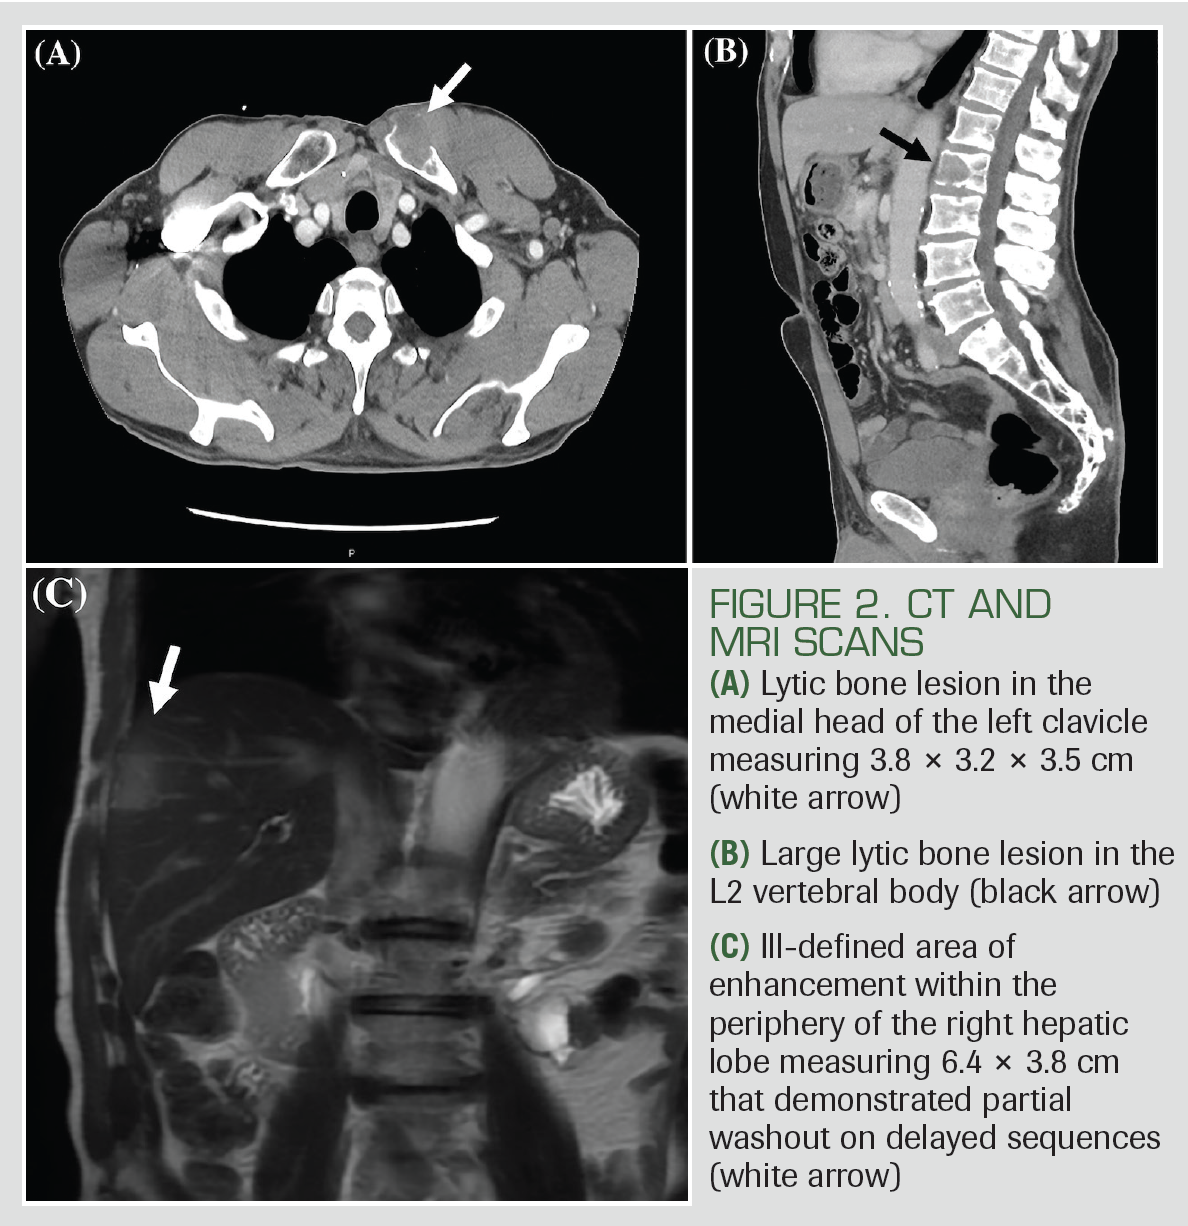

A thoracic CT scan revealed a soft tissue clavicular mass and multiple lytic vertebral lesions (Figures 2A and 2B). A CT scan of the abdomen/pelvis identified 2 poorly defined hepatic masses. Liver mass protocol MRI showed an ill-defined area of enhancement within the periphery of the right hepatic lobe that demonstrated partial washout on the portal venous phase, and the liver surface was not suggestive of cirrhosis and did not have evidence of portal hypertension (Figure 2C). Admission laboratory studies showed that aspartate aminotransferase, alanine aminotransferase, alkaline phosphatase, total bilirubin, serum albumin, prothrombin time, international normalized ratio, and platelets were within normal limits. HCV viral load was 10,400,000 IU/mL, and HIV and hepatitis B virus (HBV) core antibody/surface antigens were negative. α-fetoprotein (AFP), cancer antigen (CA)-19-9, CA-125, carcinoembryonic antigen, and prostate-specific antigen levels were within normal limits.

FIGURE 2. CT AND MRI SCANS